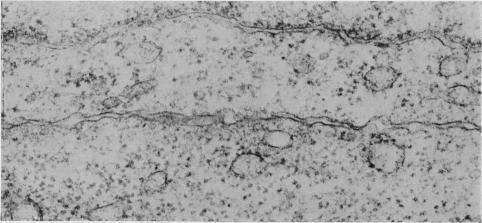

To analyse the effect of ethylenediamine tetraacetate (EDTA) on tumour cell adhesiveness, fine structure of intercellular junctions of rat ascites hepatoma cells AH136B and AH7974 (both forming cell islands in vivo) was first compared. The close contact of the apical portion of both cell islands was composed of tight junctions with a narrow gap. The close contact of the inner portion of AH136B cell islands was largely by simple apposition, while that of AH7974 cell islands had many intermediate junctions and desmosomes. Treatment with EDTA (2 mM) induced morphological alteration of simple apposition, intermediate junctions and desmosomes, but tight junctions remained intact. The effect of EDTA on such junctional complexes seemed to be partially reversible on readministration of Ca ions. Changes in desmosomes, as confirmed on AH7974 cells, were initiated by disappearance of the central disc of electron-dense materials, followed by marked opening of intercellular space and disappearance of endoplasmic laminar plaque. These results suggest that Ca ions may be concerned with maintaining the integrity of junctional complexes other than tight junctions.

为分析乙二胺四乙酸(EDTA)对肿瘤细胞黏附性的影响,首先比较了大鼠腹水肝癌细胞AH136B和AH7974(两者在体内均形成细胞岛)细胞间连接的精细结构。两个细胞岛顶端部分的紧密接触由间隙狭窄的紧密连接组成。AH136B细胞岛内部分的紧密接触主要是简单并置,而AH7974细胞岛的紧密接触有许多中间连接和桥粒。用EDTA(2 mM)处理可诱导简单并置、中间连接和桥粒的形态改变,但紧密连接保持完整。再次给予钙离子后,EDTA对这种连接复合体的作用似乎部分可逆。在AH7974细胞上证实,桥粒的变化始于电子致密物质中央盘的消失,随后细胞间隙明显增宽,内质层板消失。这些结果表明,钙离子可能与维持除紧密连接之外的连接复合体的完整性有关。